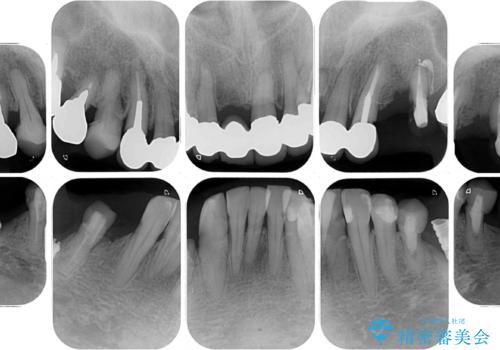

- 以前通院していた医院で、奥歯のインプラント埋入、前歯部のインビザライン矯正を行ったものの、そのまま放置してしまったとのことで来院された患者様です。

下顎前歯や上顎奥歯などをワイヤー装置により部分矯正を行い、歯列を整えた上でインプラン部分を含めてオールセラミッククラウンにて補綴治療を行うこととしました。

インプラント上の仮歯がボロボロになり、前歯に非常に負担のかかる状態であったため、早急に奥歯の仮歯を修復し、矯正治療、奥歯の補綴治療、前歯の補綴治療と順々に進めて行きました。